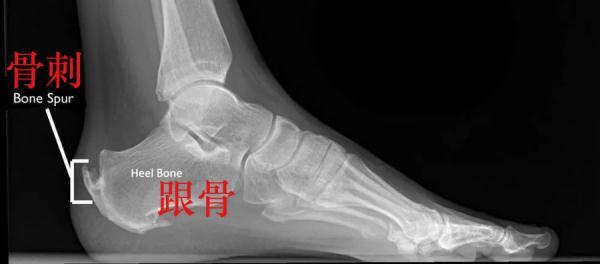

另外,在年纪较大的运动者中,经常出现的是止点跟腱炎。这种跟腱炎通常会在跟骨位置出现疼痛,并在运动后会疼痛加重。随之而来的是,跟腱附着点炎症病变,肌腱会出现钙化转变为骨质,也就是我们常说的“骨刺”。